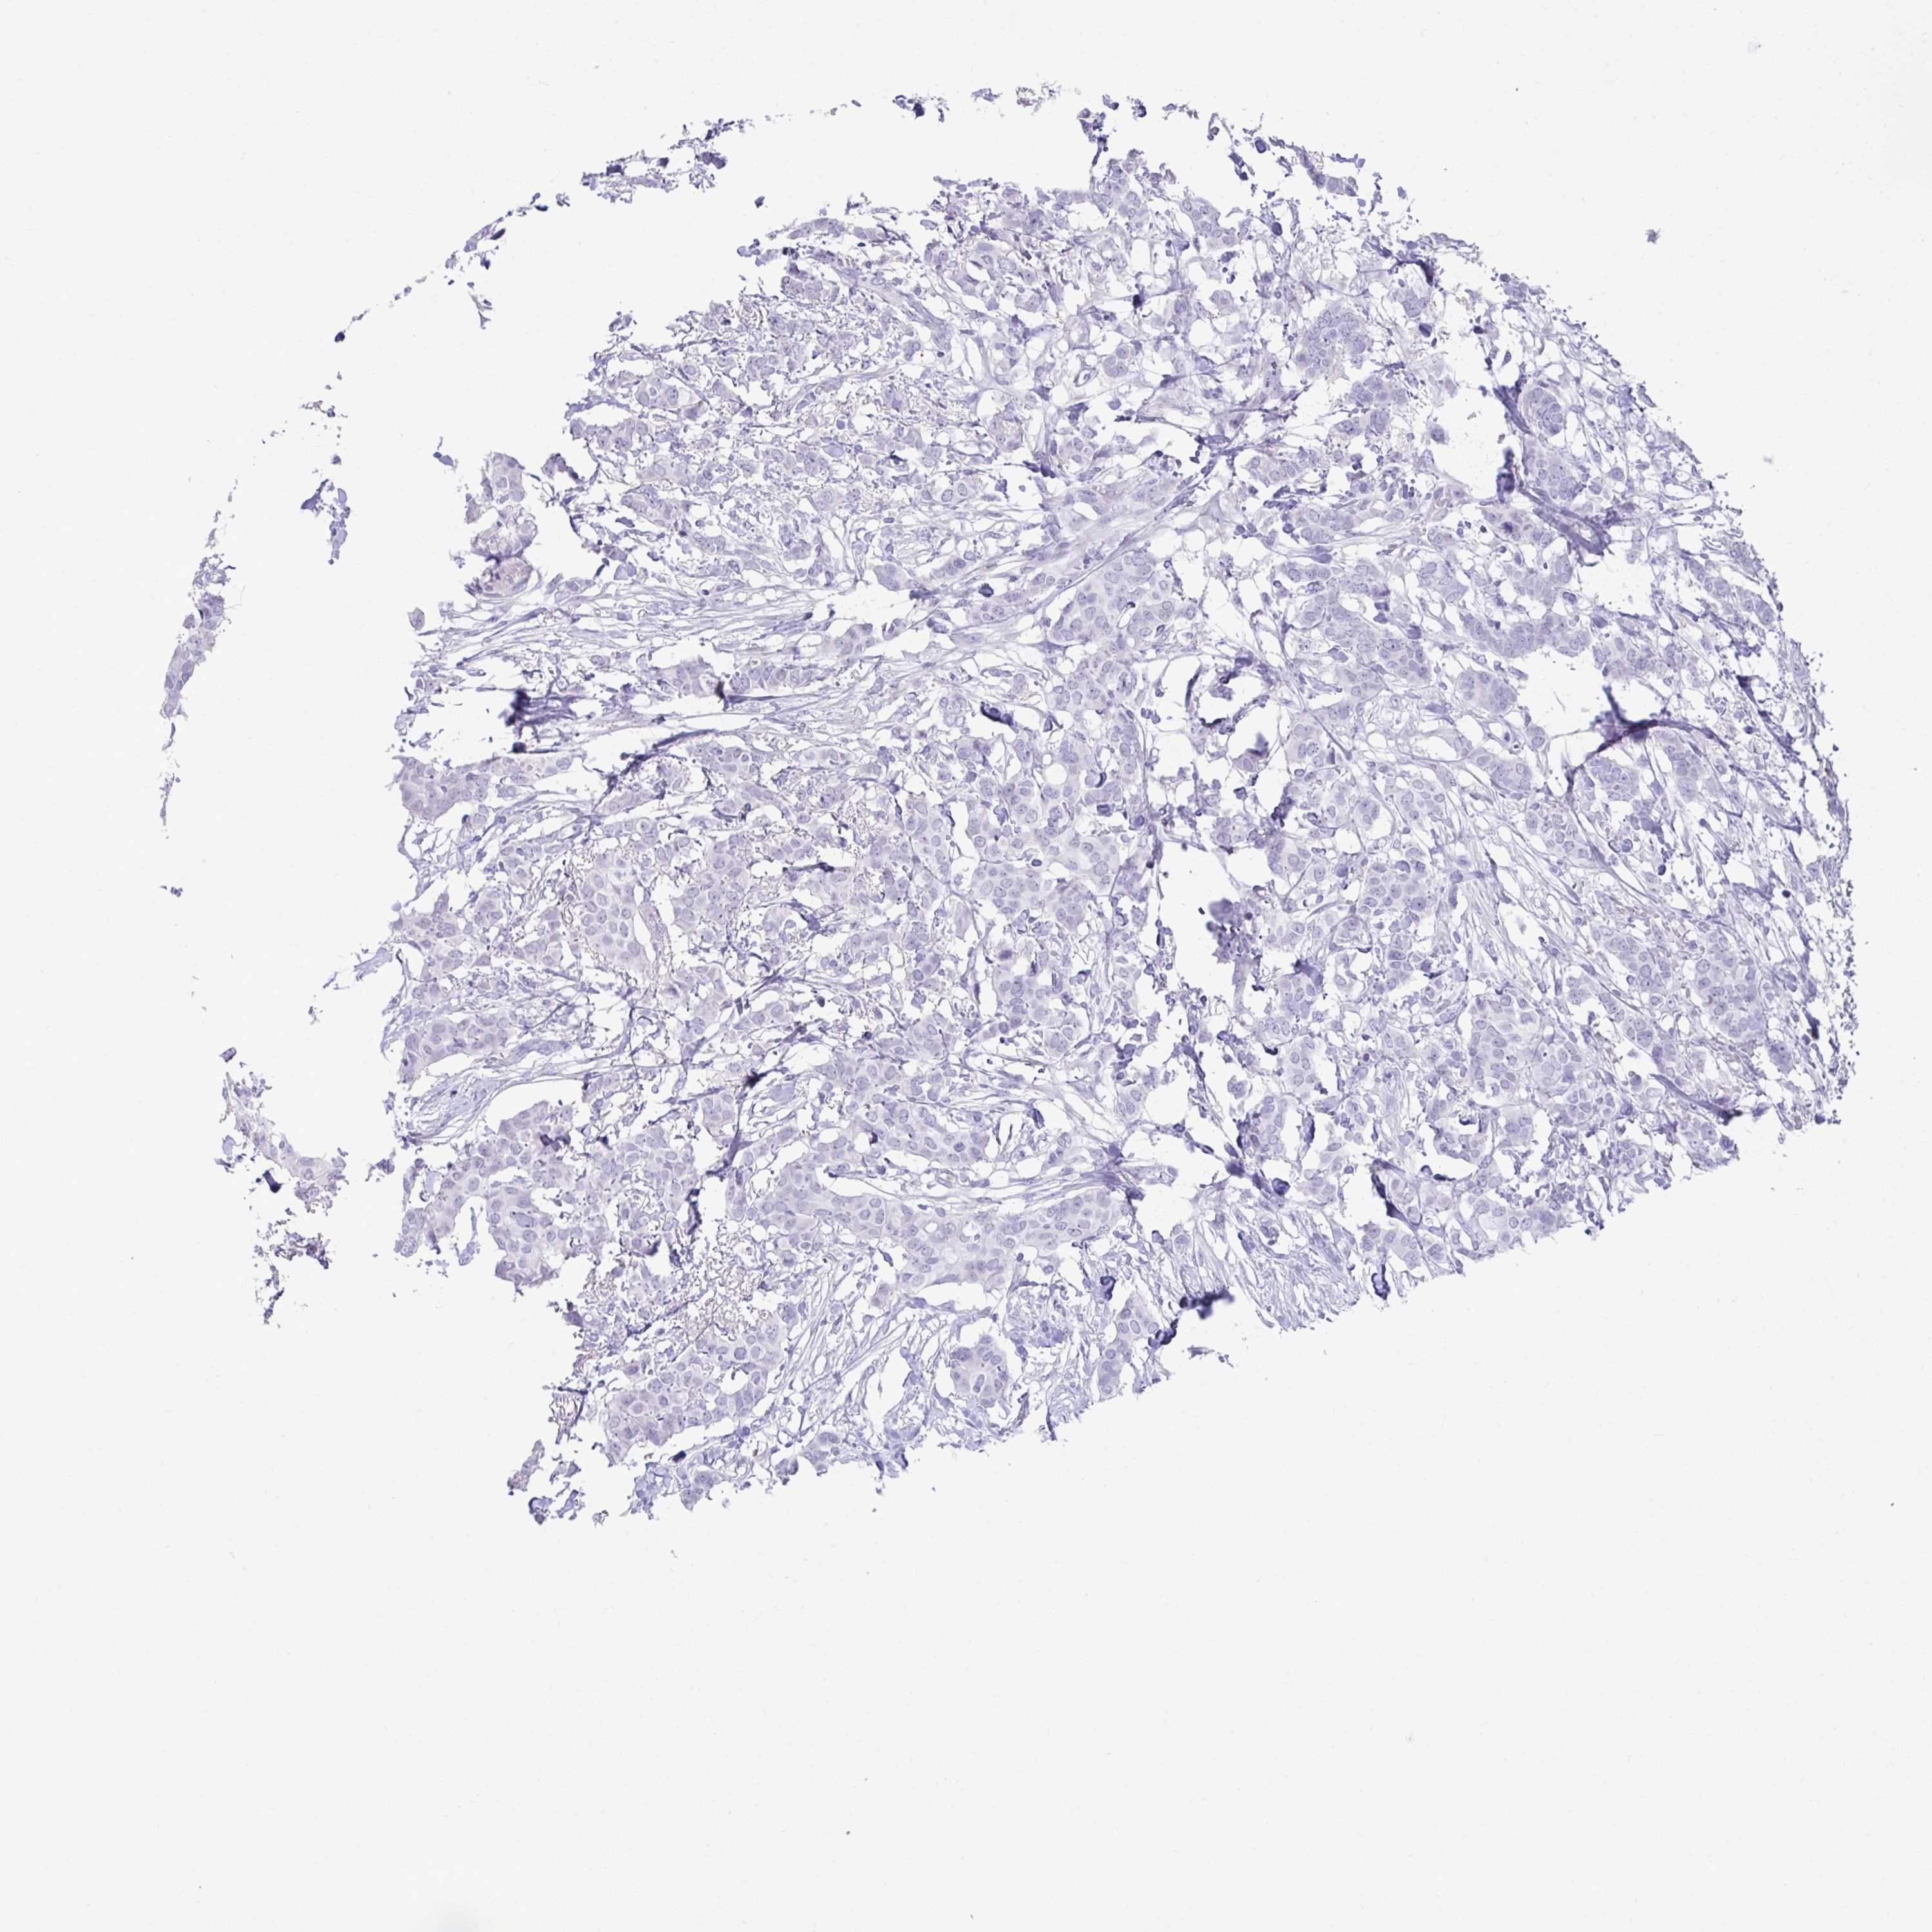

CANCER BREAST CANCER Show tissue menu

BRCA TCGA BRCA VALIDATION PROTEIN EXPRESSION

Breast cancer

Human cancer